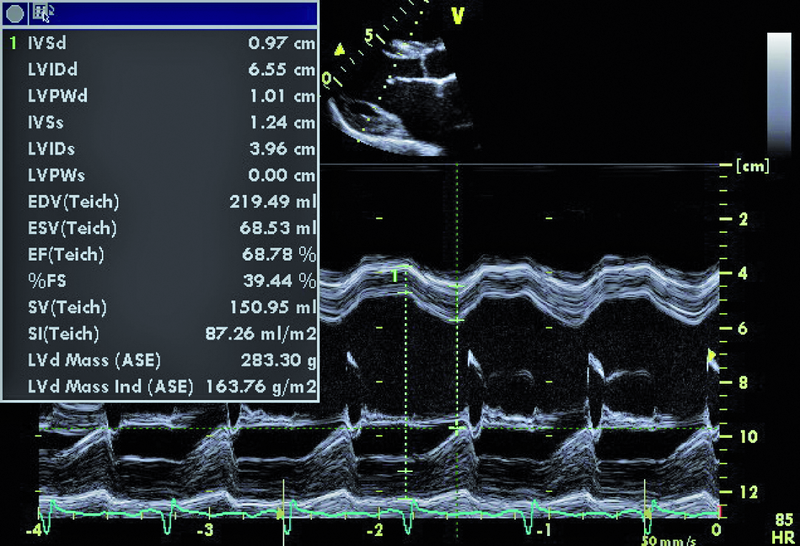

U chłopca, obecnie 16-letniego, wykonano w okresie noworodkowym zabieg operacyjny walwuloplastyki zastawki aortalnej z powodu wrodzonej stenozy. Uzyskano zmniejszenie gradientu maksymalnego z 50 do 16 mm Hg. W ciągu wielu lat obserwacji w ośrodku kardiologii dziecięcej gradienty przepływu przez zastawkę były niskie, a stan kliniczny pacjenta dobry. Sytuacja zmieniła się przed kilkoma miesiącami. Chłopiec został przyjęty do szpitala z powodu męczliwości, szybkiej częstości serca (do 90/min w rytmie zatokowym z pojedynczą ekstrasystolią komorową). Prawdopodobną przyczyną pogorszenia stanu zdrowia była przebyta wcześniej infekcja górnych dróg oddechowych. W badaniu przedmiotowym zwracał uwagę szmer holosystoliczny na koniuszku, promieniujący do pachy. W EKG rejestrowano cechy przerostu i przeciążenia mięśnia lewej komory. Wykonano cewnikowanie serca, stwierdzając nadciśnienie płucne ze średnim ciśnieniem w kapilarach płucnych 29 mm Hg. Pacjent był leczony intensywnie lekami moczopędnymi, beta-adrenolitykami i amiodaronem. Wobec braku poprawy skierowano go na oddział kardiologii dorosłych w celu rozważenia wskazań do leczenia operacyjnego. W badaniu echokardiograficznym zwracały uwagę wąskie strumienie niedomykalności zastawki aortalnej z czasem PHT wynoszącym 206 ms, istotnie powiększona jama lewego przedsionka z powierzchnią około 50 cm2, ciężkie nadciśnienie płucne z ciśnieniem skurczowym w jamie prawej komory 114 mm Hg!, rejestrowanym z małej fali zwrotnej trójdzielnej. Nie stwierdzono wady przeciekowej.

Chłopiec przebył w okresie noworodkowym zabieg walwuloplastyki aortalnej powikłany niedomykalnością zastawki (ryc. 1). Wada miała charakter przewlekły i spowodowała pojawienie się mechanizmów wyrównawczych. Jednym z nich jest zwiększenie objętości lewej komory i przyspieszenie rytmu serca. Frakcja wyrzutowa lewej komory jest zachowana (ryc. 2). Z pewnością infekcja górnych dróg oddechowych była czynnikiem inicjującym niekorzystny dla chorego przebieg zdarzeń. Ocena ciężkości niedomykalności aortalnej na podstawie parametrów ilościowych jest w tym przypadku trudna. Czas połowicznego spadku gradientu ciśnień PHT (aorta – lewa komora) oraz strumień fali zwrotnej w badaniu kolorowego doplera mogłyby wskazywać na umiarkowaną niedomykalność. Nie można jednak zapominać o możliwości zwiększenia ciśnienia rozkurczowego w jamie lewej komory, istotnie zmniejszającego gradient wsteczny i zakres fali zwrotnej. W przypadku dwustrumieniowej fali zwrotnej (jak w tym przypadku) talii cząstkowych niedomykalności nie sumuje się. Podobnie ograniczone zastosowanie w tym wypadku (ekscentryczne fale zwrotne) ma metoda ERO. Najprawdopodobniej wtórną do niedomykalności aortalnej wadą jest niedomykalność mitralna wynikająca z poszerzenia jamy lewej komory i poszerzenia pierścienia zastawki mitralnej. Niedomykalność mitralna także wydaje się co najwyżej umiarkowana (ryc. 3). Należy pamiętać, że i w tym wypadku szerokość strumienia fali zwrotnej zależy od wysokości ciśnienia w jamie przyjmującej, czyli w lewym przedsionku. Na podstawie przedstawionego materiału (ryc. 4-6) można stwierdzić, że nadciśnienie płucne u chłopca (postkapilarne) jest ciężkie, a ciśnienia uległy istotnemu zwiększeniu w porównaniu z wartościami stwierdzanymi wcześniej podczas cewnikowania serca (ciśnienie rozkurczowe płucne 54 mm Hg, średnie 74 mm Hg!). Warto zwrócić uwagę na profil spływu z żył płucnych. Zaznacza się w nim bardzo krótka faza odzwierciedlająca wyłącznie rozkurczowy napływ krwi do lewego przedsionka. Zwiększona objętość jamy przedsionka, wysokie ciśnienie krwi w niej panujące oraz ograniczona podatność ściany sprawiają, że w fazie skurczu komory nie rejestruje się napływu do jamy przedsionka. Podobnie bardzo wysokie ciśnienie w układzie żył płucnych sprawia, że nie obserwuje się przepływu wstecznego w związku z ciągle zachowanym skurczem przedsionka (rytm zatokowy). Chłopca zakwalifikowano do operacji dwuzastawkowej z powodu ciężkiej niedomykalności aortalnej i mitralnej. Zabieg implantacji zastawki biologicznej o średnicy 23 mm w ujście aortalne oraz pierścienia o średnicy 32 mm w ujście mitralne przyniósł dobry efekt.